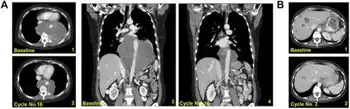

Soft tissue sarcoma

In 2007, the European Commission gave authorization for the marketing of trabectedin, "for the treatment of patients with advanced soft tissue sarcoma, after failure of anthracyclines and ifosfamide, or who are unsuited to receive these agents".[8][5] The European Medicine Agency's evaluating committee, the Committee for Medicinal Products for Human Use (CHMP), observed that trabectedin had not been evaluated in an adequately designed and analyzed randomized controlled trial against current best care, and that the clinical efficacy data were mainly based on patients with liposarcoma and leiomyosarcoma. However, the pivotal study did show a significant difference between two different trabectedin treatment regimens, and due to the rarity of the disease, the CHMP considered that marketing authorization could be granted under exceptional circumstances.[9] As part of the approval PharmaMar agreed to conduct a further trial to identify whether any specific chromosomal translocations could be used to predict responsiveness to trabectedin.[10]

In 2015, (after a phase III study comparing trabectedin with dacarbazine[12]), the US FDA approved trabectedin (Yondelis) for the treatment of liposarcoma and leiomyosarcoma that is either unresectable or has metastasized. Patients must have received prior chemotherapy with an anthracycline.[13]